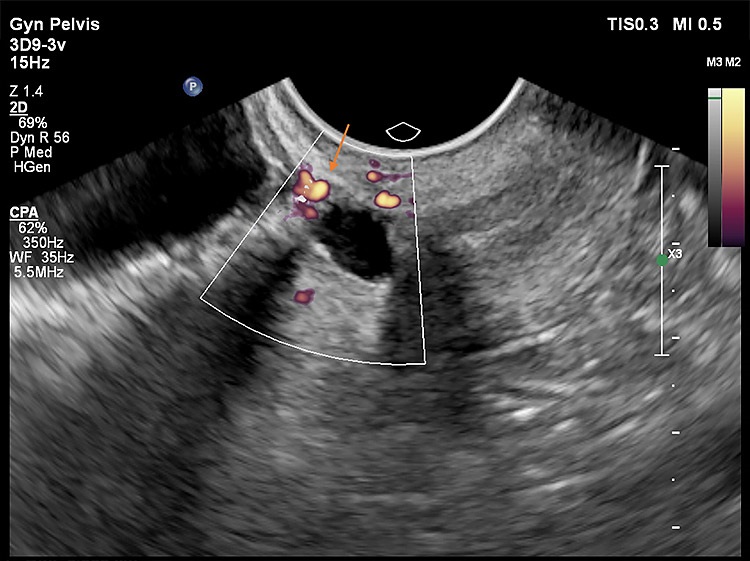

Στις παρακάτω εικόνες από ενδοκολπικό υπέρηχο φαίνονται παραδείγματα επιπέδου τρία προηγμένης τεχνολογίας υπερηχογραφικής μελέτης όπου σημαντικές λεπτομέρειες σε ό,τι αφορά τη θέση, το μέγεθος και την ανατομική συσχέτιση της Ισθμοκήλης, είναι εμφανή με καθαρό τρόπο, επιτρέποντας την εκτίμηση κατά πόσο μπορεί να γίνει χειρουργική επέμβαση ή όχι, και αν ναι με ποια τεχνική. Όλες οι εικόνες έχουν παραχθεί με υπερηχογραφική μηχανή Philips Elite, Costas Panayotidis operator.

Εικόνα 5: δείχνει Power Doppler μελέτη αγγείων που περιλαμβάνει το σημείο επούλωσης της προηγηθείσας καισαρικής αλλά και τη σχέση των αγγείων αυτών με την κύστη ισθμοκήλης